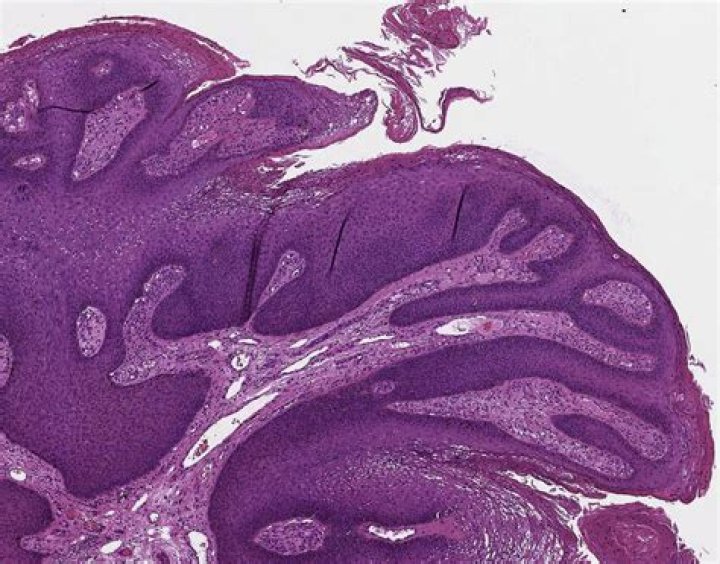

Keratoacanthomas are rapidly growing, squamoproliferative benign tumors that resemble squamous cell carcinoma. They begin as round, firm, reddish or skin-colored papules that develop into dome-shaped nodules with a keratin-filled crater (Figure 3). They may grow to 1 to 2 cm over weeks or months.

What kind of tumor is a squamoproliferative lesion?